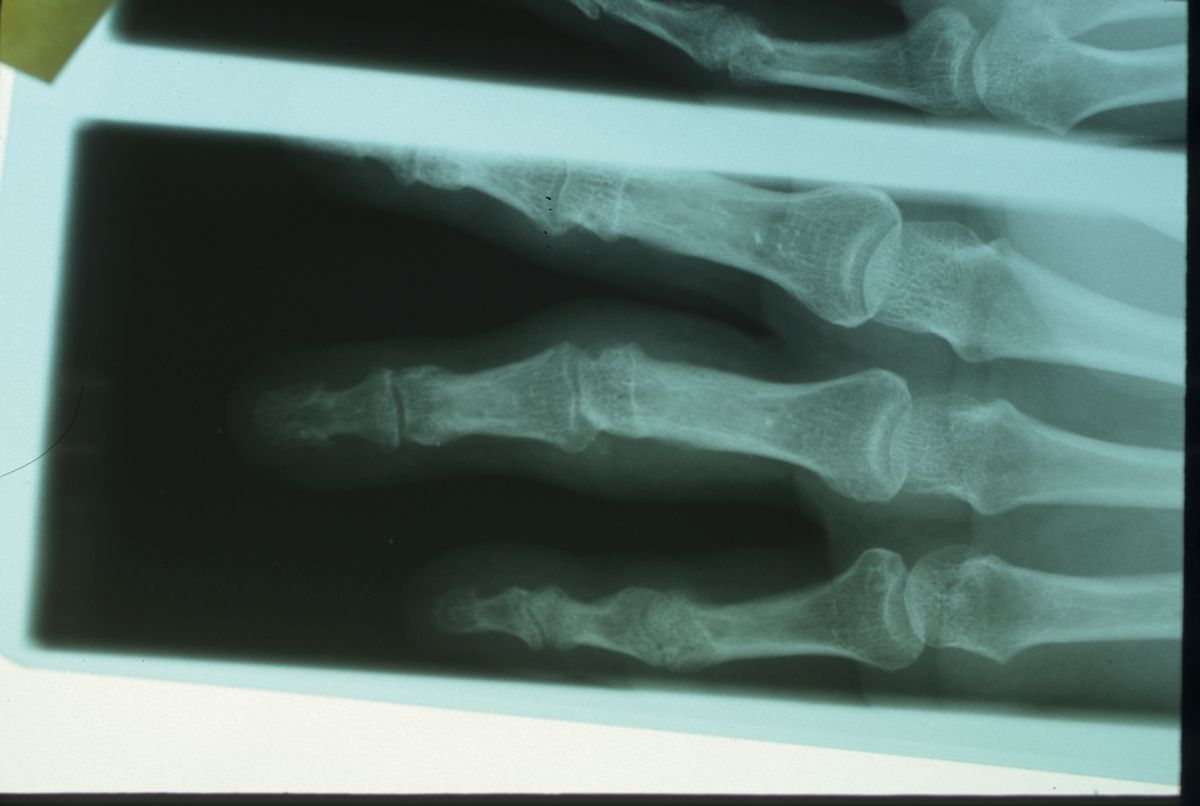

At the same time, what was a nodule in the right palm progressed to right ring finger contracture:

Hesitant to have fasciectomy, and too anxious to agree to an awake procedure, the patient delayed treatment four more years before deciding to have treatment for what had become a severe contracture.